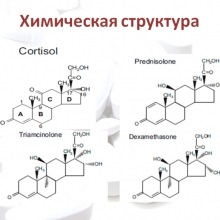

Ma már nehéz megtalálni egy orvos, aki nem használja a gyakorlatban glükokortikoidok. És ezért foglalkozni ezeknek káros hatása használat szükséges nem ritka. Az egyik ilyen hatás a fejlesztési úgynevezett „iatrogén Cushing-szindróma” vagy „iatrogén város